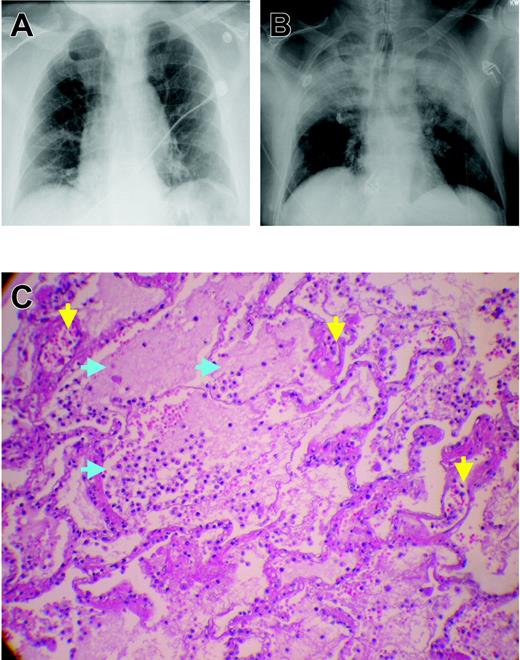

Although TRALI develops within 6 hours of transfusion,6,8-10 most occurrences take place during transfusion or within the first 1 or 2 hours after it.8,9,11-14 Clinical findings of TRALI consist of the rapid onset of tachypnea, cyanosis, dyspnea, and fever (1°C or higher.).6,9 Although hypotension was reported in most patients in the early clinical studies of TRALI, it is not a consistent finding.6,11,12 Auscultation of the lungs reveals diffuse crackles and decreased breath sounds, especially in dependent areas.6,9 Physiologic findings include acute hypoxemia, with PaO2/FiO2 less than 300 mm Hg, and decreased pulmonary compliance despite normal cardiac function.6,9,12,15 Radiographic examination reveals diffuse, fluffy infiltrates consistent with pulmonary edema (Figure 1).6,9 In short, the clinical diagnosis of TRALI is identical to that of acute lung injury (ALI), as described by Bernard et al16 (Table 1). Treatment consists of aggressive respiratory support, including supplemental oxygen and mechanical ventilation.6,9,12 Milder forms of TRALI have been described that require prompt delivery of supplemental oxygen alone.11,12,17,18 As with ALI and the acute respiratory distress syndrome (ARDS), there is no role for treatment with corticosteroids or diuretics.9,12,18-20 One infant was successfully treated with extracorporeal membrane oxygenation (ECMO) for a particularly severe clinical presentation.21

Chest x-rays and microscopic pathology examination of a patient with fatal TRALI. (A) Chest x-ray of the patient before surgery demonstrating low lung volumes with subsegmental bibasilar atelectasis, no evidence of pleural effusion, focal consolidation, or pneumothorax, and normal cardiomediastinal silhouette. (B) Chest radiograph at the time TRALI was recognized, which demonstrates extensive bilateral areas of consolidation in the mid and upper lobes of the lung consistent with aspiration or edema with a normal cardiac silhouette, new since the previous examination earlier on the same day. The endotracheal tube tip is 6 cm above the carina, the nasogastric tube is coiled within the hypopharynx before extending to the proximal trachea, and the right internal jugular introducer sheath tip overlies the proximal superior vena cava. These extensive areas of consolidation in mid and upper lobes are most concerning for noncardiogenic pulmonary edema. (C) Plastic-embedded histologic sections of the lungs at autopsy were stained with hematoxylin and eosin, toluidine blue, or Jones stains, and were examined by light microscopy under an OptiPhot-2 microscope equipped with a 20 ×/0.4 objective lens (Nikon, Melville, NY). Images were photographed with a Nikon CoolPix 4500 camera and acquired with Apple Mac OS × 10.3.5 (Apple, Cupertino, CA) running Portfolio 7 software (Extensis, Portland, OR). There is significant extravasation of PMNs into the alveoli and air spaces with interstitial and intra-alveolar edema (blue arrows). Toluidine blue and Jones stains demonstrate dilated capillaries and a prominence of inflammatory neutrophils in the capillaries and air spaces (yellow arrows). Histologic findings are consistent with early acute respiratory distress syndrome.

The mortality rate from TRALI ranges from 5% to 25%; rates in the lower end of the range are more common.9,11,14,20 Most patients recover within 72 hours; however, the data regarding TRALI are limited, and the attendant morbidity and mortality may be underappreciated because of lack of recognition and underreporting.9,11,14,20 Autopsy specimens have demonstrated pulmonary findings consistent with ARDS, including widespread leukocyte infiltration with interstitial and intra-alveolar pulmonary edema, hyaline membrane formation, and destruction of the normal lung parenchyma (Figure 1).11,22-26 In addition, in epidemiologic studies of ARDS, blood transfusion was implicated as the most common risk factor for the genesis of ARDS, and a number of these patients may represent severe cases of TRALI.22